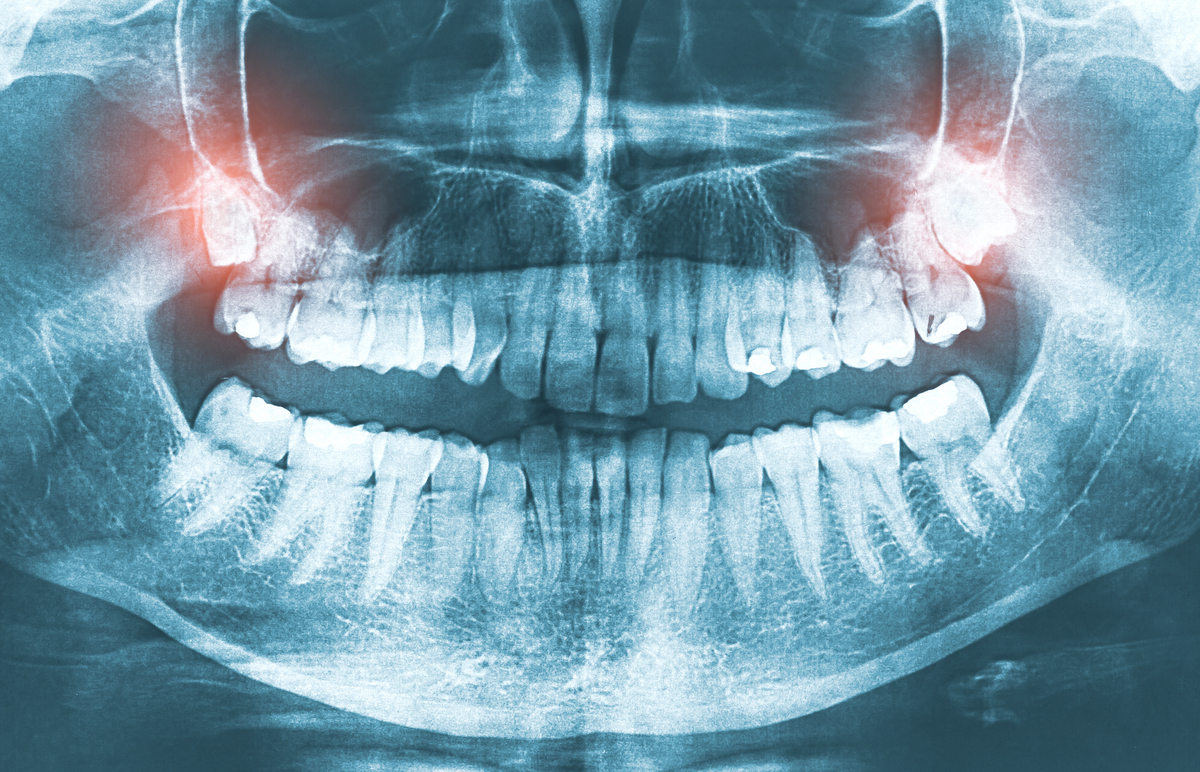

Your visit begins with a gentle exam and digital X-rays that show the exact position of your wisdom teeth. We explain what we see in clear, simple terms and help you understand whether removal is recommended or if monitoring is enough for now. Our goal is always to help you make confident, informed decisions.